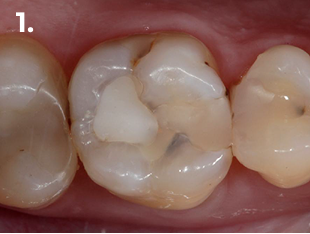

Esame clinico e radiografico:

• Restauro composito occluso-mesiale

• Carie distale profonda

Diagnosi: Pulpite reversibile

Il paziente si presenta alla visita riferendo fastidio nella zona del primo quadrante. L’esame clinico e radiografico evidenzia la presenza di una carie distale profonda, portando alla diagnosi di pulpite reversibile. Al fine di ottenere un adeguato punto di contatto sia mesiale che distale, si è proceduto alla rimozione completa del restauro preesistente.

Fig. 1 Immagine clinica iniziale